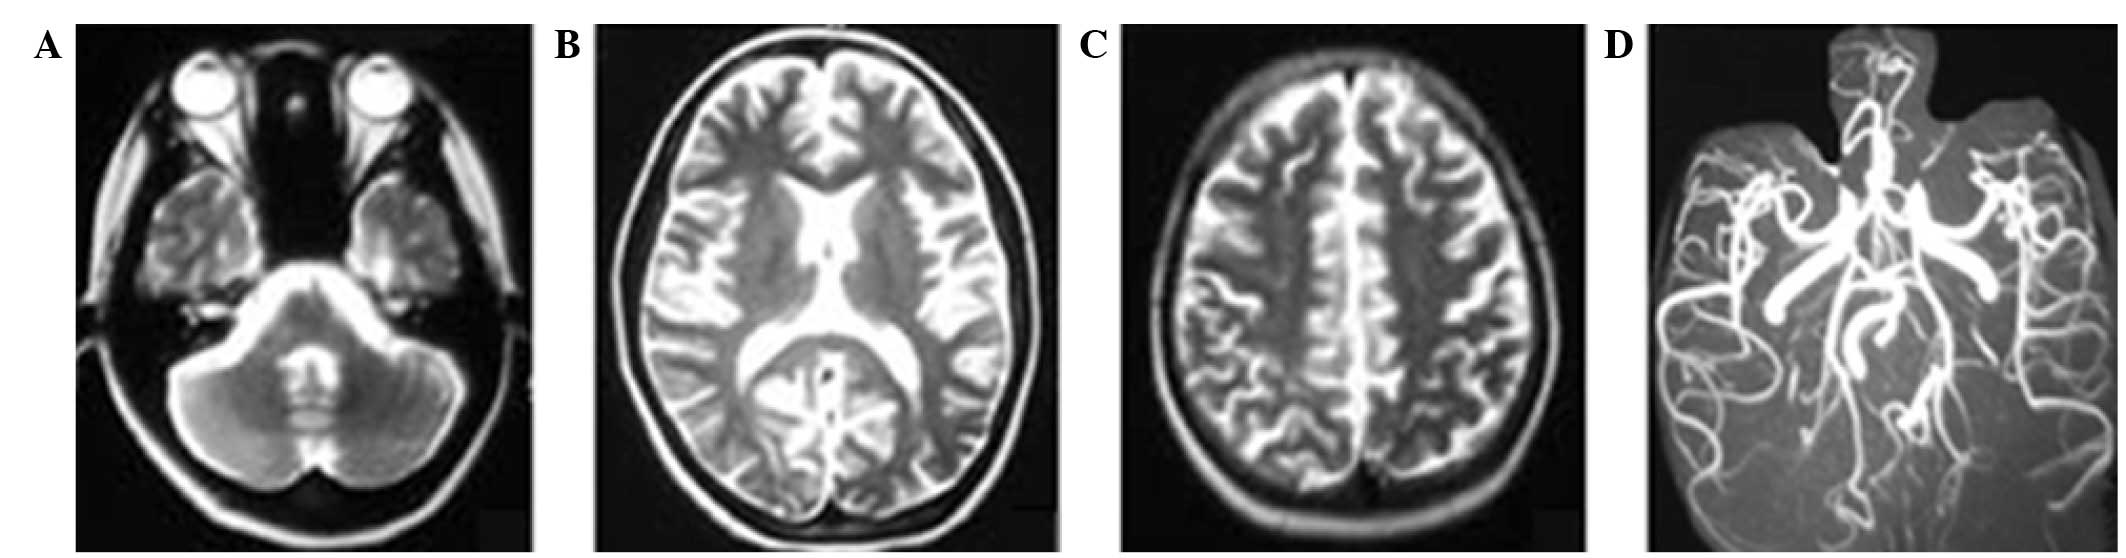

On day 4 after hospital admission, the patient received further head MRI and magnetic resonance arteriography/magnetic resonance venography (MRA/MRV) scans. The hyperintensity zones on T2-weighted images of the subcortex and white matter in the cerebellum, and occipital, frontal and parietal lobes were markedly decreased. The MRA scan revealed cerebral vascular focal vasodilation and vasoconstriction features with a string-of-beads appearance (Fig. 2), predominantly in the vessels of the posterior circulation of the brain. In addition, there was no intracranial sinus thrombosis; however, the MRV indicated venous sinus dilation (Fig. 2). Based on the results of tests, the diagnosis of reversible posterior encephalopathy induced by LPE was suspected. The patient was administered cefoperazone (4 mg per day), nimodipine (10–20 mg per day) and mannitol (250–500 ml per day). The temperature and blood pressure were normalized following treatment, and the patient experienced no further seizures during the remaining of the hospital stay. On day 11 after admission, the patient received further head MRI examination that indicated an almost complete resolution of the previous abnormalities (Fig. 3). Subsequently, the patient was discharged without any neurological sequela. The follow-up neurological examination after 1 month showed no abnormalities. During the two months follow-up examinations, no neurological symptoms were found.